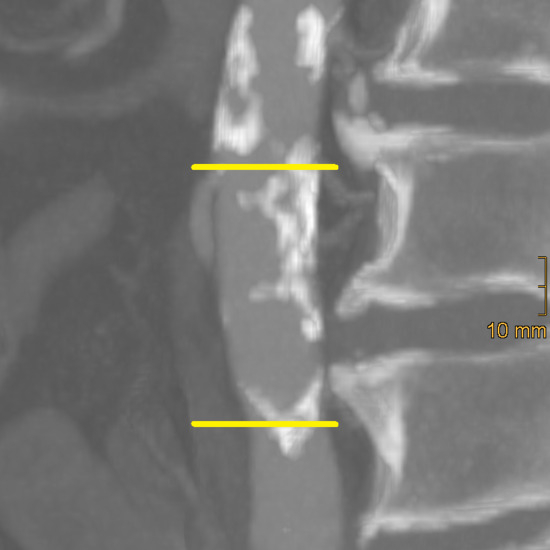

Background: Vascular calcification is a frequent consequence of ageing and is associated with an increased risk of cardiovascular disease. This study aimed to compare two rapid scoring systems for quantifying calcification of the distal abdominal aorta and iliac arteries and to investigate correlations with increasing age. Methods: Patients aged ≥65 years who sustained pelvic trauma between 2003 and 2023 and underwent computed tomography (CT) were included in this retrospective study. Patients were categorised into three age groups (65–74, 75–84, ≥85). The abdominal aorta calcification score (AACS) and the common, external, and total iliac artery calcification scores (CIACS, EIACS, TIACS) were assessed on cross-sectional images and classified into three severity grades (mild, moderate, severe). Results: A total of 224 patients (mean age 78.8 ± 8.5 years; 62% female) were included. Significant differences between age groups were identified for hypertension (p < 0.001), osteoporosis (p < 0.001), atrial fibrillation (p = 0.015), chronic heart failure (p = 0.004), chronic kidney disease (p < 0.001), neurocognitive disorders (p < 0.001), and anticoagulant therapy (p = 0.002). Calcification severity increased with age across all vascular territories (EIACS p = 0.006; others p < 0.001). In multivariable linear regression, age remained the strongest adjusted predictor of calcification across all vascular regions (β = 0.323–0.376, all p < 0.001). Significant positive correlations were found between aortic and iliac calcifications (all p < 0.001), strongest between AACS and CIACS (ρ = 0.78, CI 0.719–0.835) and TIACS (ρ = 0.745, CI 0.676–0.807). Corresponding categorical associations were most pronounced between AACS and CIACS. Conclusions: The evaluated calcification scores were strongly correlated and demonstrated clear age-dependent trends. Given their simplicity and applicability to routine CT imaging, these methods may provide practical tools for assessing vascular ageing. Full article